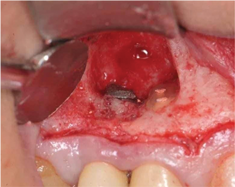

Report of a case. A 45-year-old male patient was referred with pain, redness, and swelling around an implant in the position of the maxillary right second premolar. The implant had been in clinical function for 3 years. The patient had a history of endodontic treatment and tooth loss and subsequent implant treatment in the region. Radiographic examination showed a radiolucency around the apical portion of the implant and the adjacent tooth. The implant was clinically stable and the neighboring tooth No. 4 was considered to have a periapical lesion. Initially, the patient received antibiotics (clindamycin 300 mg, three times daily) and was followed up for 2 weeks. After this, the patient was scheduled for surgical exploration of the implant area. Treatment comprised elevation of a full-thickness flap, curettage of the apical lesion, irrigation with saline, and removal of the apical portion of the implant and apicoectomy of the adjacent tooth (Figure 3 and Figure 4), including a guided bone regeneration (GBR) procedure with a cancellous particulate allograft and 20 mm x 30 mm pericardium membrane. Granulation tissue was sent for histopathology analysis, which revealed a periapical inflammatory infection. At the 4-month follow-up increased radiographic bone density could be observed consistent with the formation of bone not only around the implant apex but also along the root of tooth No. 5 (Figure 5).

Fig 4. Intraoperative situation after apical resection of implant and tooth.

Figure 4